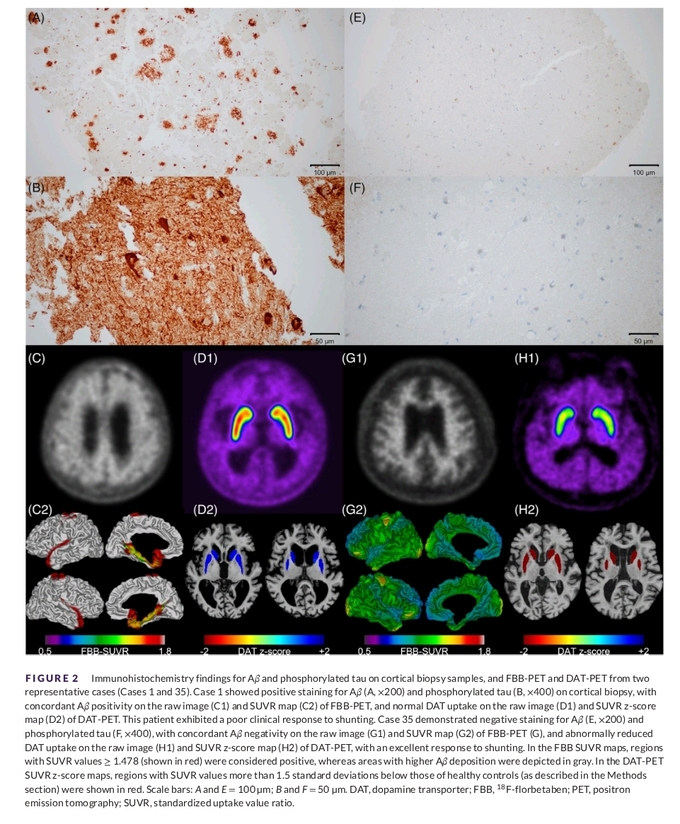

연구팀은 이러한 의문을 해결하기 위해 2017년부터 2022년까지 세브란스병원에서 VP 션트 수술을 받은 특발성 정상압 수두증 환자 58명을 분석했다. 수술 중 전두엽 피질에서 소량의 뇌 조직을 채취해 알츠하이머병 관련 단백질을 면역염색으로 확인했고, 일부 환자에게는 아밀로이드 PET과 도파민 수송체(DAT) PET 검사를 시행해 퇴행성 병리와 도파민 신경 기능을 함께 평가했다.

그 결과, 전체 환자의 약 40%에서 알츠하이머병 단백질이 확인됐다. 특히 수술 중 시행한 뇌 조직 검사 결과는 아밀로이드 PET 검사 결과와 95% 이상 일치해, 제한된 조직 검사만으로도 실제 뇌 병리를 매우 정확히 반영할 수 있음을 확인했다.